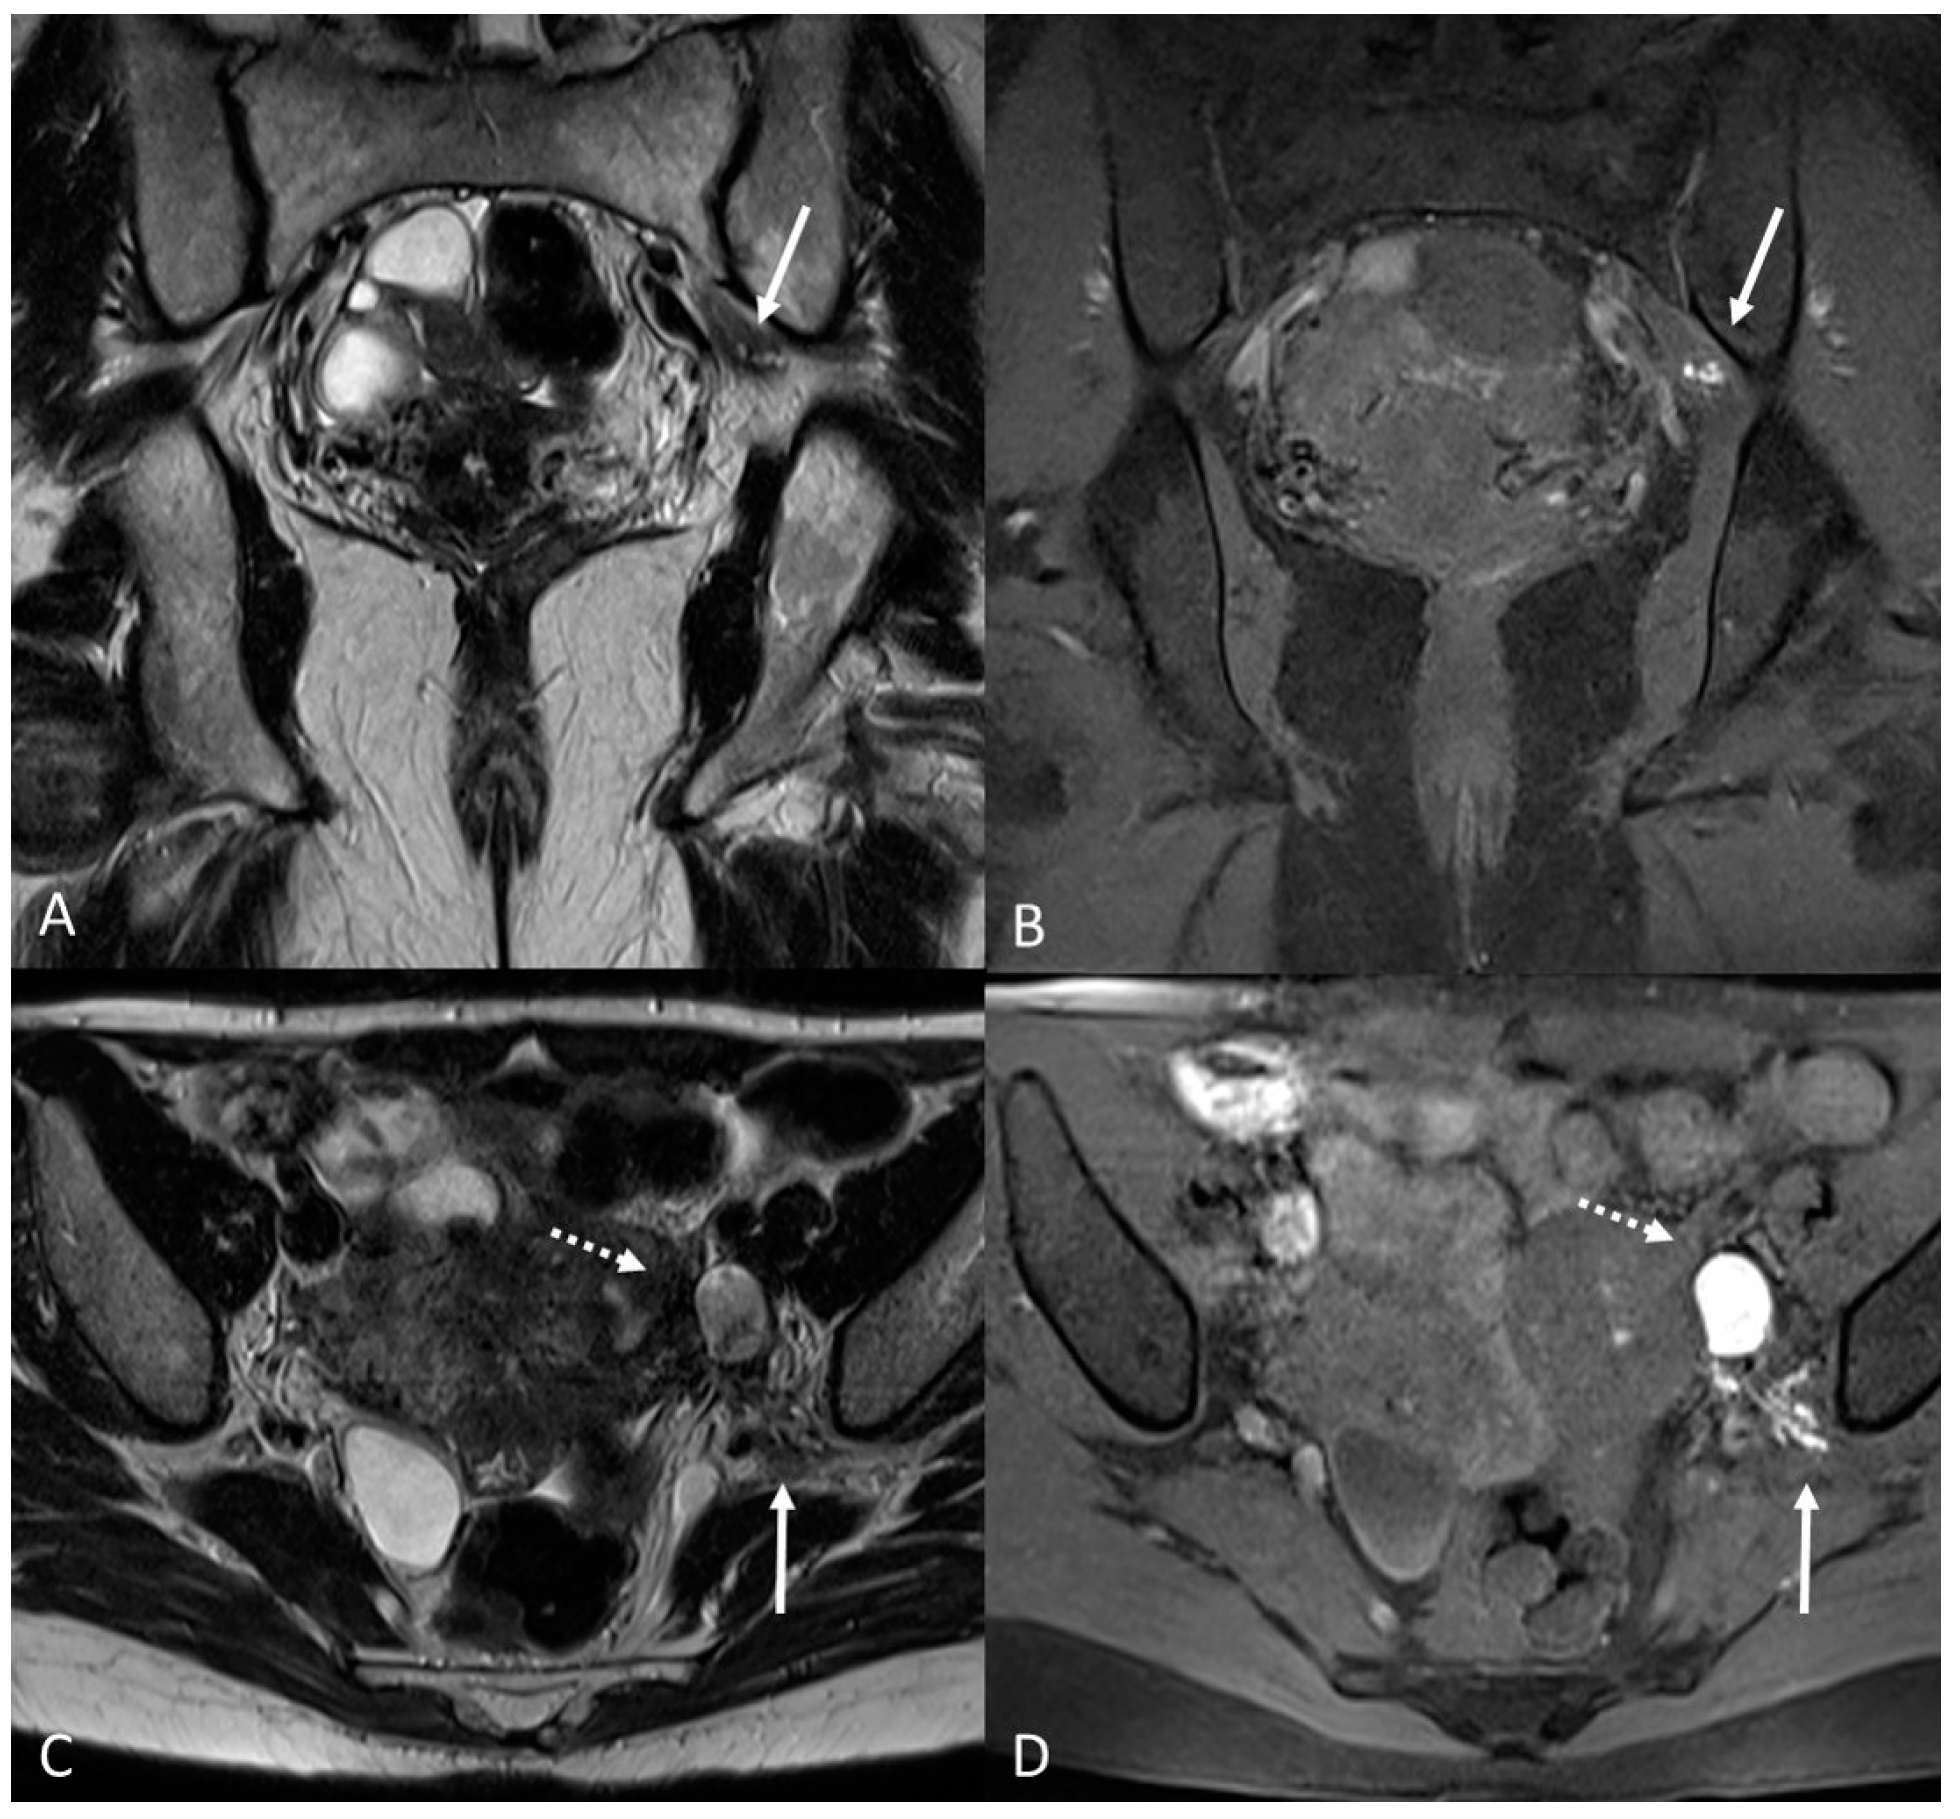

Figure 4.

Retrocervical endometriosis plaque, intestinal localization, kissing ovaries with bilateral ovarian endometriomas. (A,B) Axial T2WI; (C) Coronal T2WI. Hypointense retrocervical plaque (white arrowhead in (A)) localized in the uterine torus with involvement of the utero-sacral ligaments. Adhesions involve both ovaries with bilateral endometriomas (white arrows), which are prolapsed in a retro-uterine position and adhered to the utero-sacral ligaments and the recto-sigmoid junction. There is also an eccentric anterior parietal thickening in the recto-sigmoid junction suggestive of intestinal endometriosis lesion (white dotted arrow in (A)).

On an MRI, lesions appear as irregular thickness or nodules within the intestinal serosa or muscularis propria, hypointense at T2WI. They rarely affect the submucosa or the mucosa, and if infiltrated, we can observe edema and swelling in the area [7] (Figure 5 and Figure 6).

Figure 5.

External adenomyosis and intestinal endometriosis localization in 49-year-old female with story of multiple laparoscopy surgery. Sagittal T2WI shows a hypointense ill-defined subserosal mass in the posterior myometrium with hyperintense foci (long white arrow), suggestive for external adenomyosis, that cause retracting phenomena towards the anterior wall of the rectum. Additionally, there is deep endometriosis of the posterior compartment with hypointense nodule involving the serous and muscular layers of the anterior wall of the rectum (short white arrow).

Figure 6.

Retrocervical localization, intestinal mushroom cap sign and isthmocele in a 40-years old female. Retrocervical endometriosis localization (white dotted arrow), intestinal “mushroom cap sign” (white arrows) and isthmocele (black arrow).